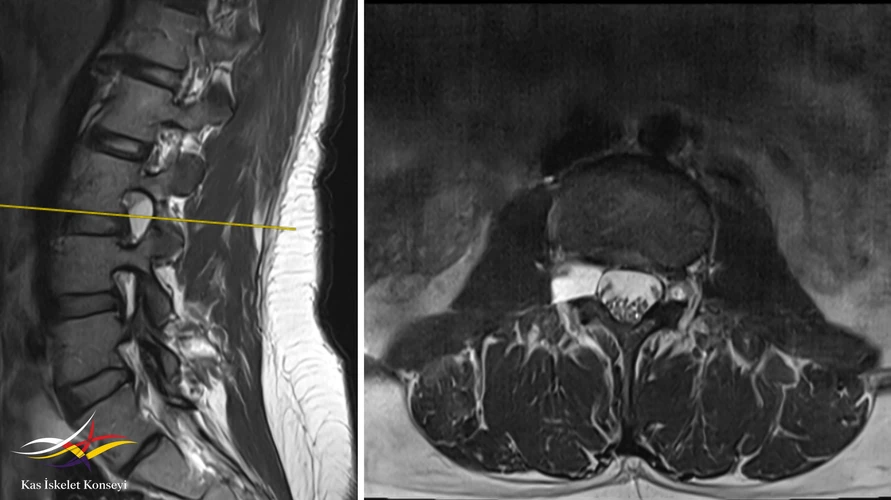

Resim 2. Sagittal ve aksiyal T2 ağırlıklı inceleme.

L3-4 seviyesinde sağ nöral foramen yerleşimli lezyon, tüm sekanslarda BOS intansitesine eş dansitede olmasına binaen bir perinöral kist olarak değerlendirildi. Bu lezyonun komşu kökü basarak semptomatik olabileceği, ancak bu yerleşimdeki bir kistin hastadaki gibi bel ve sol bacak ağrısından çok, sağ bacak ağrısı ve sağ L3 kök bulguları yapmasının bekleneceği düşünüldü. Bel ve sol bacak ağrısının L5-S1 seviyesindeki ılımlı disk dejenerasyonuna bağlı olabileceği öngörüldü. Sağ bacakta radiküler bir ağrı olmadıkça perinöral kiste yönelik radyolojik takibe gerek görülmedi.